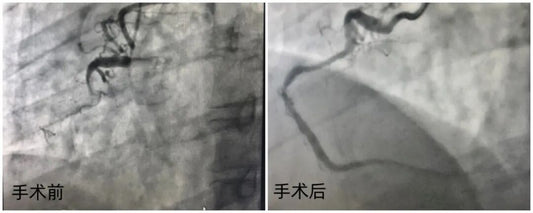

Fuwai Hospital demonstrates technical excellence in treating a 43-year-old patient’s complex CTO via a scaffold-free strategy. This case highlights the role of rigorous lesion preparation in achieving revascularization under complex...